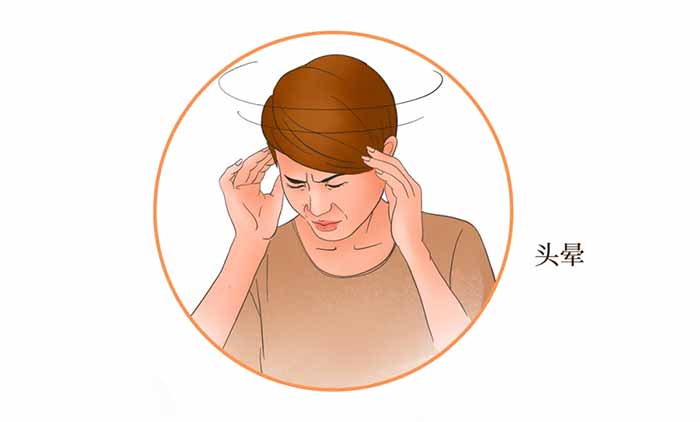

提起脑梗死,很多人会立即想到“突发半身不遂、口眼歪斜、言语不清”等典型表现。但后循环缺血的症状却常常“不按常理出牌”。

上海蓝十字脑科医院【同济大学附属脑科医院(筹)】脑血管病二科4B病区主任潘登博士指出:后循环梗死的症状往往不典型,易与其他疾病混淆,可能表现为:头晕或眩晕、视物重影、呕吐、行走不稳、言语含糊、口周或面部麻木、肢体麻木等。

正因为这些症状与耳石症、眼部疾病甚至焦虑症有相似之处,导致许多患者辗转于眼科、耳鼻喉科等多个科室,延误了最佳诊治时机。

▲ 后循环梗死的症状往往不典型